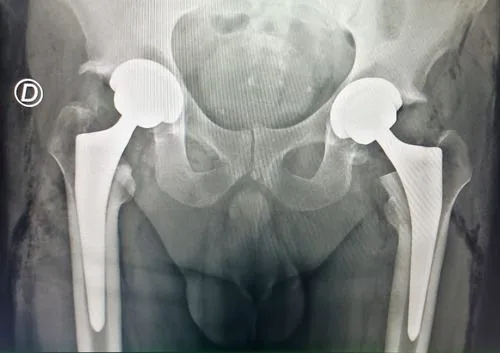

Preoperatorio

Postoperatorio

Reemplazo bilateral de cadera en un tiempo. Internación de 24 horas con alta deambulando con andador. Resolución completa del dolor bilateral y recuperación funcional temprana.